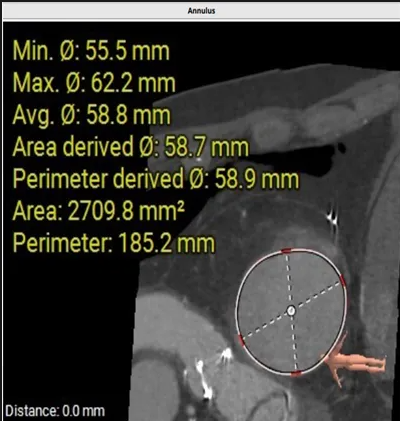

術前心臟CT評估

三尖瓣環(huán)平均周長徑58.8mm,最大直徑62.2mm